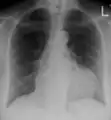

- Ultrasounds showing a pericardial effusion in someone with pericarditis

- A pericardial effusion as seen on CXR in someone with pericarditis

The diagnosis of tamponade can be confirmed with trans-thoracic echocardiography (TTE), which should show a large pericardial effusion and diastolic collapse of the right ventricle and right atrium. Chest X-ray usually shows an enlarged cardiac silhouette ("water bottle" appearance) and clear lungs. Pulmonary congestion is typically not seen because equalization of diastolic pressures constrains the pulmonary capillary wedge pressure to the intra-pericardial pressure (and all other diastolic pressures).